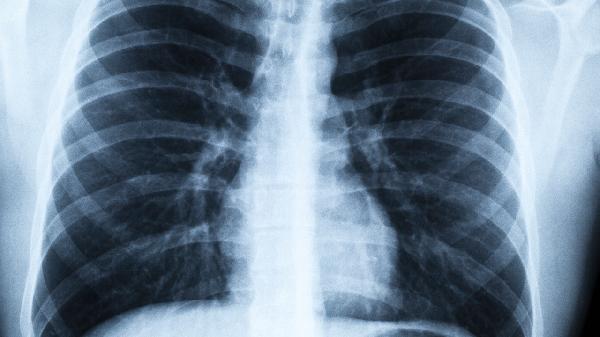

62岁男子确诊肺癌晚期!医生提醒:卧室这3种物品,赶紧扔掉

62岁的老张怎么也没想到,一次普通的体检会改变他的生活轨迹。CT报告单上"肺部占位性病变"几个字格外刺眼,更让他震惊的是医生接下来的话:"这些常见物品可能是帮凶..."其实我们每天有三分之一时间在卧室度过,有些潜伏的健康杀手就藏在枕边。